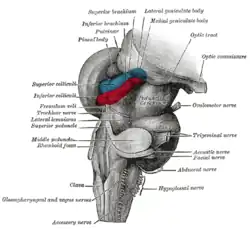

Hind- and mid-brains; postero-lateral view.

Hind- and mid-brains; postero-lateral view. Figure showing the mode of innervation of the Recti medialis and lateralis of the eye.